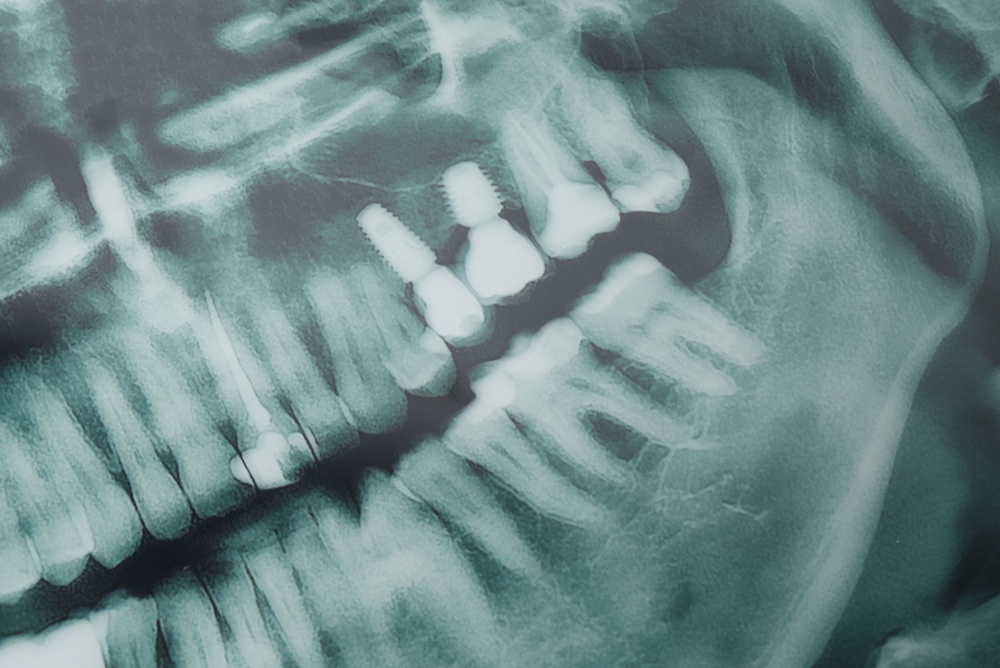

A dental implant has three main parts: the implant body (usually titanium or zirconia) that fuses with bone, the abutment that connects the implant to the visible tooth, and the crown or prosthesis you chew with. Each piece has a different role and lifespan: the implant fixture is rated to last longest, while crowns or prosthetics wear and may need replacement sooner.

Keep implants clean with daily brushing and flossing or interdental brushes, and get professional cleanings and X-rays at recommended intervals. Use a night guard if you grind, quit smoking, and follow medical advice for diabetes or other health issues. Regular check-ups catch small problems before they become major.